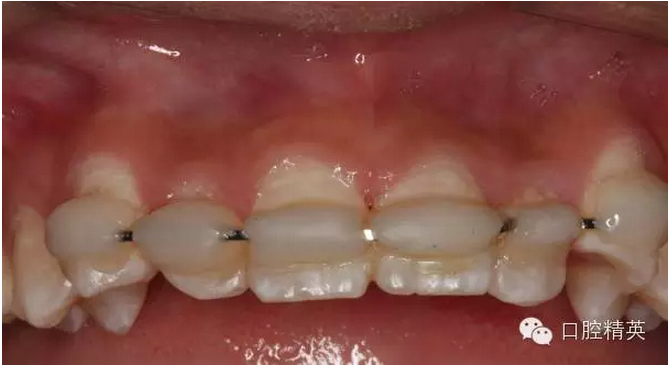

圖1.術(shù)前患者口內(nèi)像、牙槽窩輕度收縮、血凝塊穩(wěn)定、無(wú)滲出。

圖2.口內(nèi)整體影像